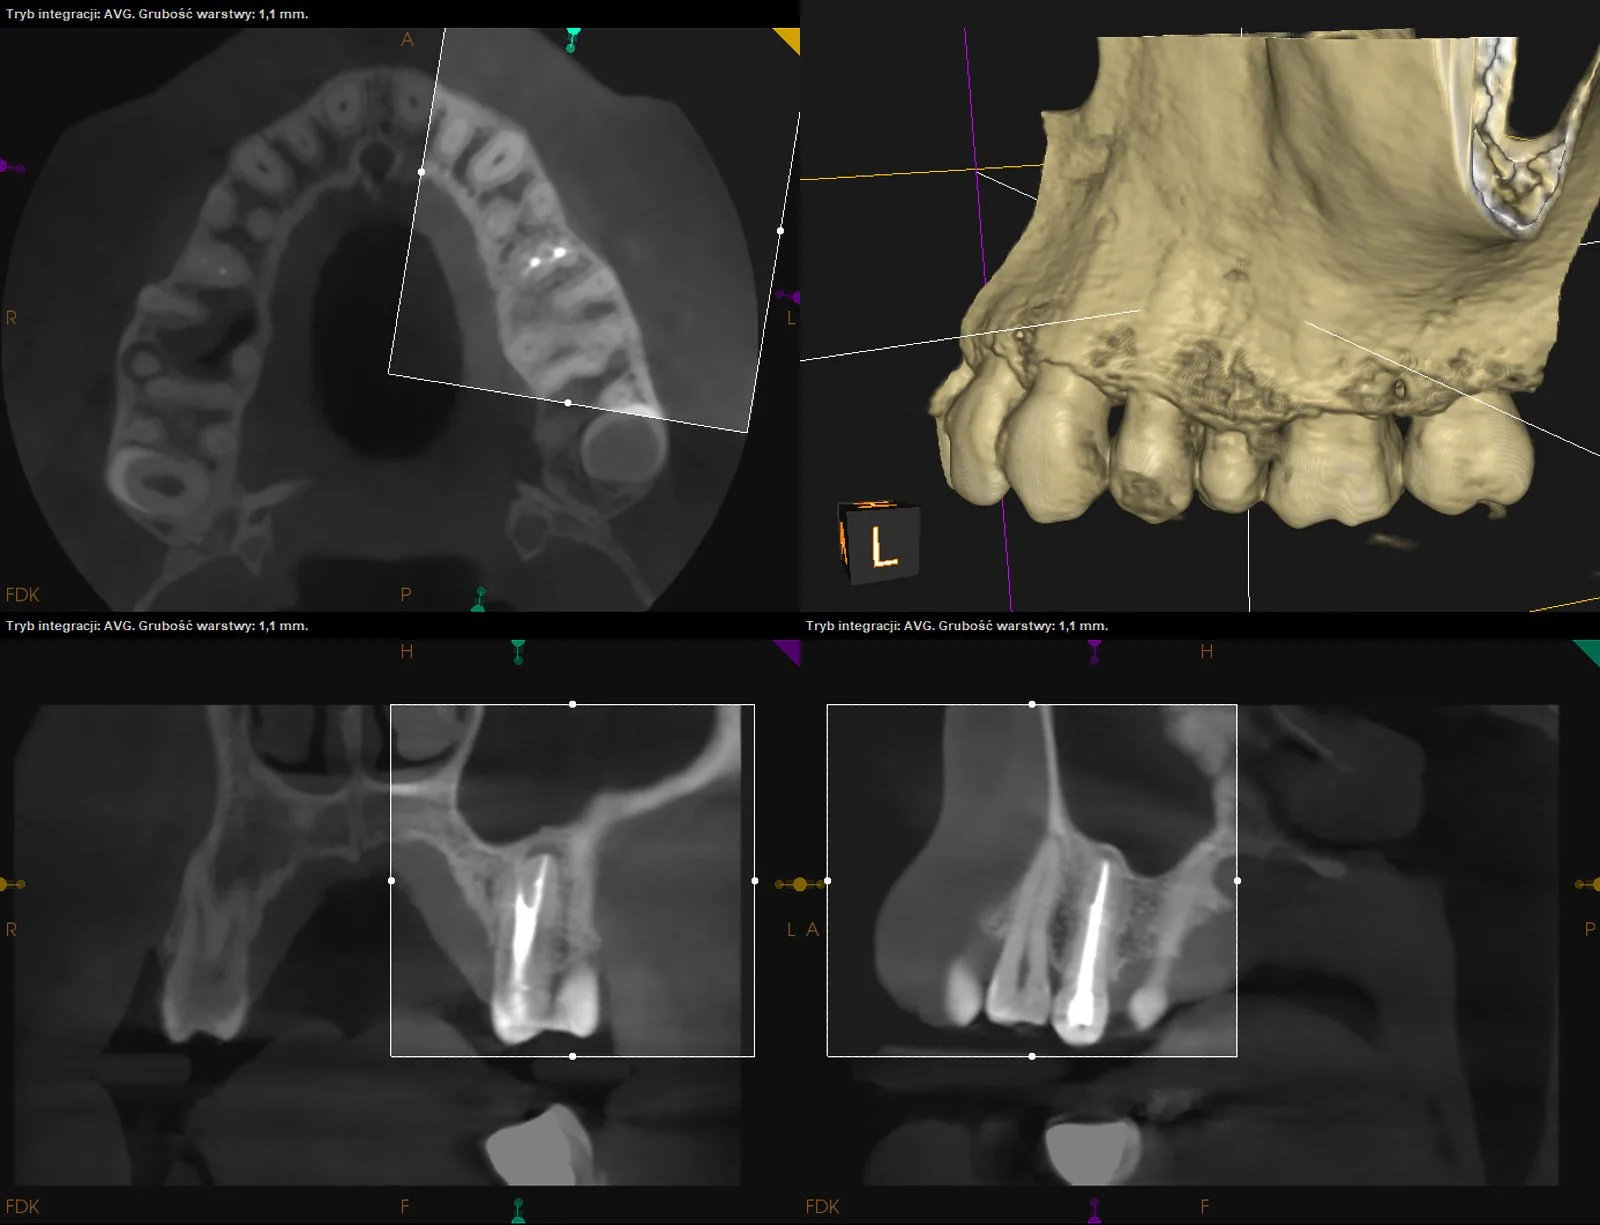

Reendo d.26. Wykonano ponowne leczenie kanałowe systemu korzeniowego z odnalezieniem i udrożnieniem pominiętego przy pierwotnym leczeniu kanału MB2 (anatomicznie typ VI w klasyfikacji Vertucciego).